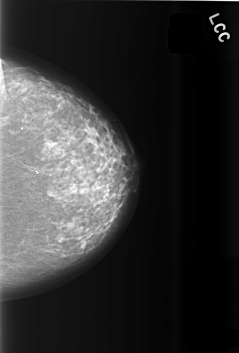

C_0473_1.LEFT_CC

LEFT_CC LINES 5640 PIXELS_PER_LINE 3816 BITS_PER_PIXEL 12 RESOLUTION 50 NON_OVERLAY